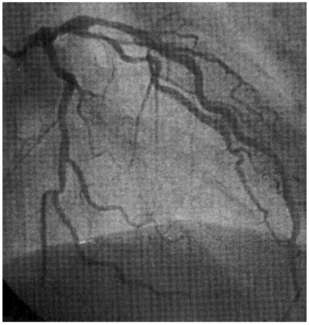

Our primary endpoint was radial artery occlusion. In terms of access, we used either right radial or left radial, but it was distal. The way we did this procedure was ultrasound-guided, sticking in the anatomic snuff box. In the initial part, we were using a 5F sheath; later on, we have a 6F, 7 centimeters, so it's a short sheath so that you don't damage the more proximal part of those radial arteries. Also, it will stay in the distal part of the radial artery and several centimeters into it. And of course, we took all of the precautions, vasospastic agents, and giving heparin if it is diagnostic only, and patent hemostasis, all of those.

Our primary endpoint was radial artery occlusion, and we measured that using either a reverse Barbeau test or, if the patient came back for a second procedure, whether we were able to re-access the same site. We had 71 patients, 66% were on hemodialysis, and our radial artery occlusion rate was 0%, so none of the patient had radial artery occlusion. I just want to clarify that the radial artery occlusion we were looking at was proximal radial artery occlusion; it's not at the site of the distal radial artery access, but we were looking at proximal radial. The reason we looked at the proximal radial artery is because that's the place we want to spare these patients, so they can have future arteriovenous (AV) fistula access there.